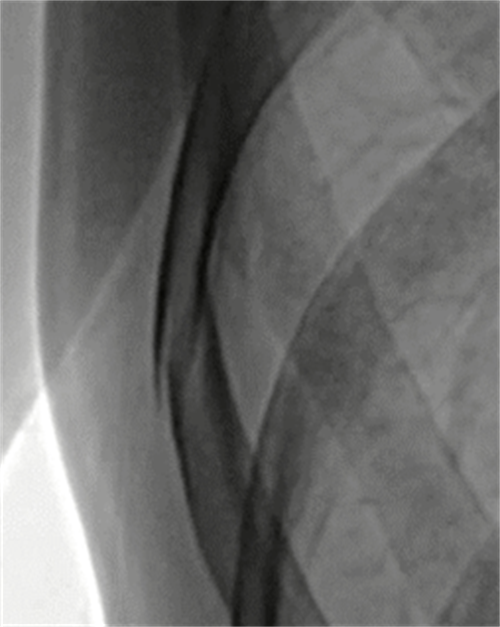

②三维化。三维是在动态的基础上实现的。那么为什么要将动态DR往三维化方向发展呢?原因就是目前常规动态DR在临床上有一定临床应用局限性。传统二维平片它极易受到投照角度以及摆位的影响导致漏诊和误诊,而三维检查能全面的呈现被检查部位在多个角度下的三维影像信息,能够提供精准且直观量化的测量数据辅助临床做出精准诊疗。(三维扫描重建图像)